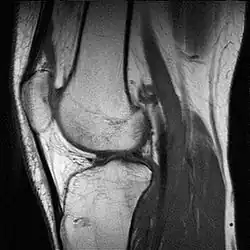

Met een MRI kan een hernia zo goed zichtbaar gemaakt worden, dat gebleken is dat heel veel mensen er klachtenvrij mee rondlopen. Het is dan ook zaak niet te snel over te gaan tot onderzoek en behandeling. Met MRI zijn de weke delen (alles behalve bot) van gewrichten goed af te beelden, zoals

- Knie: meniscus, kruisbanden enzovoorts